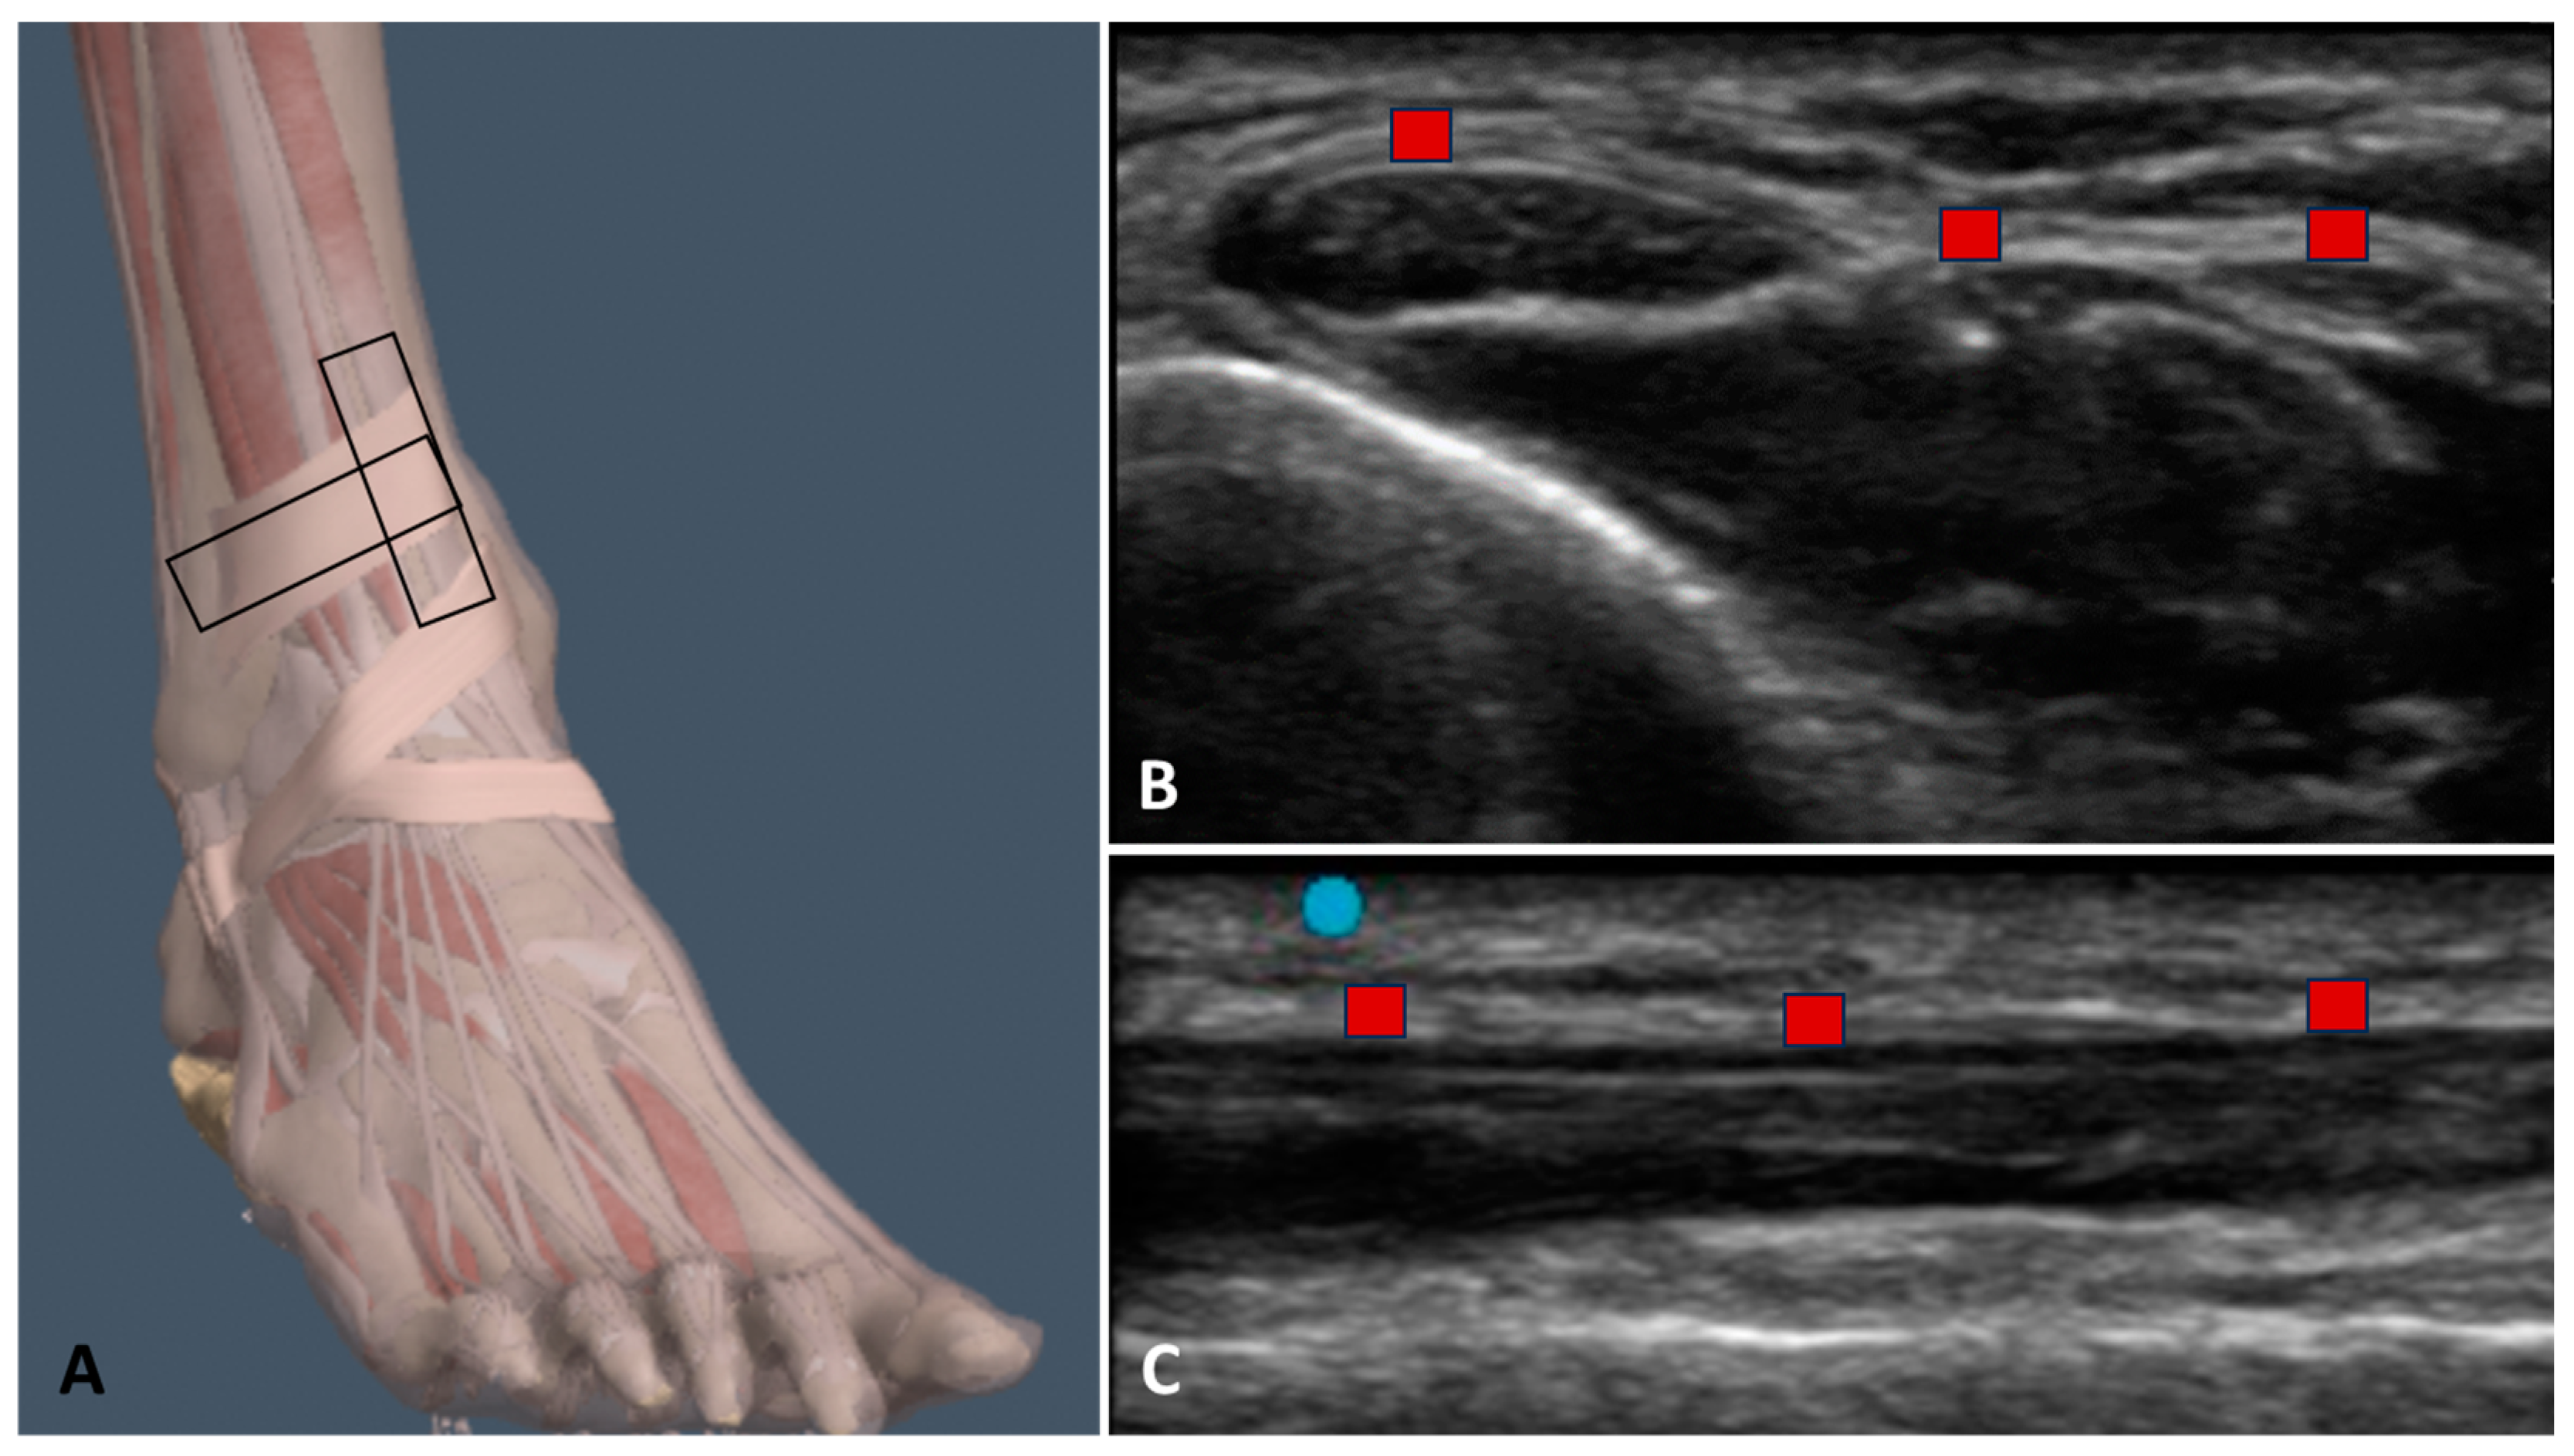

2.3. Ultrasound Examination Measurements

- Pirri, C.; Stecco, C.; Güvener, O.; Mezian, K.; Ricci, V.; Jačisko, J.; Fojtik, P.; Kara, M.; Chang, K.V.; Dughbaj, M.; et al. EURO-MUSCULUS: European Musculoskeletal Ultrasound Study Group in Physical and Rehabilitation Medicine. EURO-MUSCULUS/USPRM Dynamic Ultrasound Protocols for Ankle/Foot. Am. J. Phys. Med. Rehabil. 2024, 103, e29–e34. [Google Scholar] [CrossRef] [PubMed]